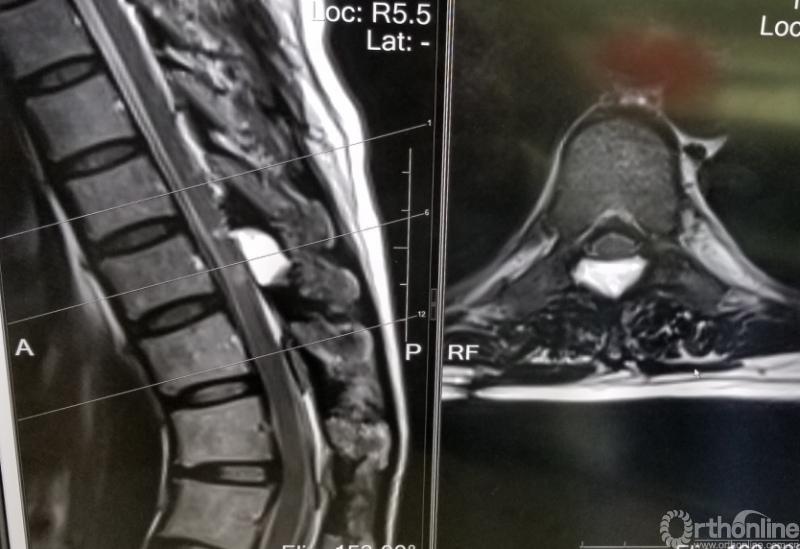

脊柱内镜手术通常作为首选手术方法,能有效地减压并进行相应的处理。适用于胸椎管狭窄症,如胸椎黄韧带肥厚症、胸椎间盘突出症、胸椎后纵韧带骨化症等,尤其适合单节段狭窄者。